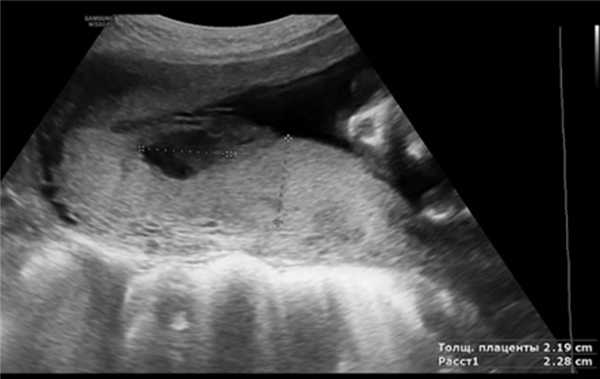

В подгруппу 1А вошли 25 беременных с единичными расширениями МВП размером менее 20 мм (рис. 3). Среди соматической патологии, фигурирующей в клиническом диагнозе, встречались ГСД — 3 (12%) наблюдения, хронический гепатит — у 2 (8%) пациенток, бронхиальная астма — у 1 (4%), ВПГ- и ЦМВ-инфекция — у 4 (16%), кондиломатоз — у 4 (16%). Невынашивание отмечено в анамнезе у 3 беременных, СЗРП I степени — у 2, СЗРП III степени — в 1 наблюдении при обострении ВПГ- и ЦМВ-инфекции в данную беременность. Перинатальных потерь не было.

Рис. 3. Единичные расширения МВП плаценты.